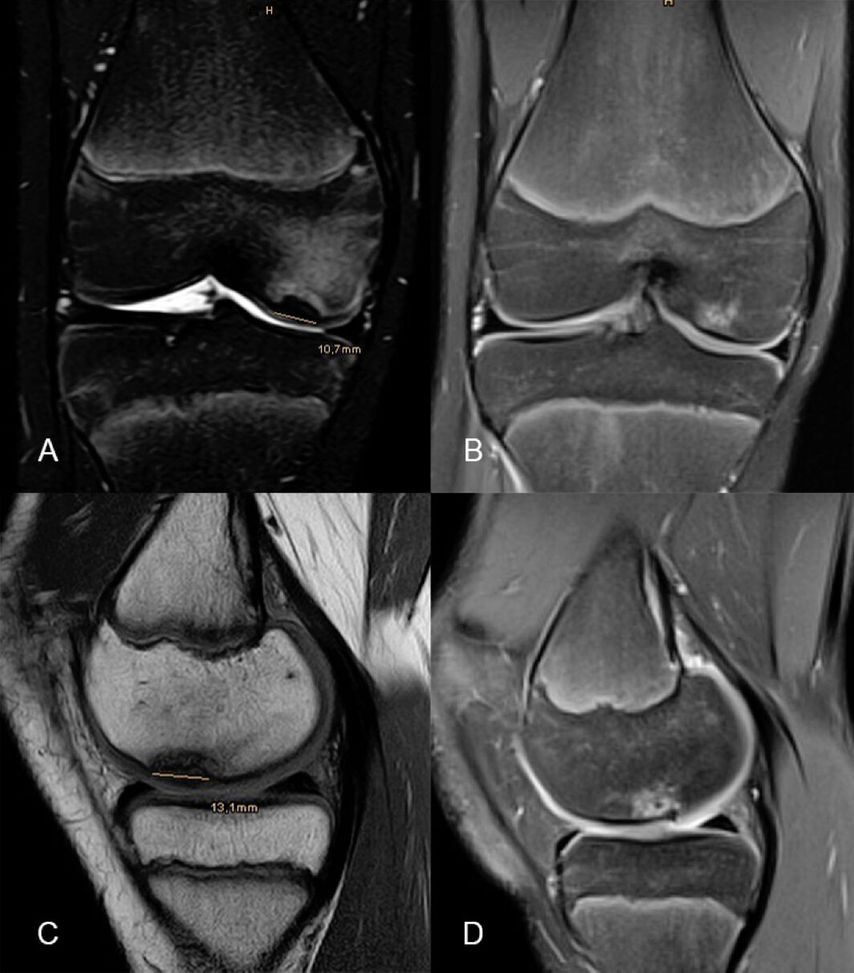

Abb. 4: 13-jähriger männlicher Patient mit einer instabilen Osteochondritis-dissecans-Läsion am posterolateralen medialen Femurkondyl präoperativ (A, D), 3 Monate (B, E) sowie 12 Monate (C, F) nach Refixation mittels Shark-Screw

Abb. 5:13-jähriger männlicher Patient mit einer instabilen Osteochondritis-dissecans-Läsion am posterolateralen medialen Femurkondyl präoperativ (A, C) sowie 12 Monate (B, D) nach Refixation mittels Shark-Screw